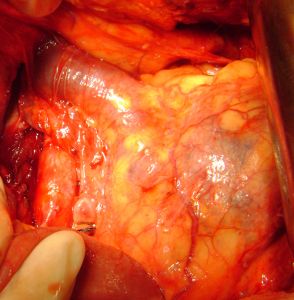

У пациентки 64 лет удалили левую почку, пораженную опухолью. Опухолевый тромб полностью заполнял почечную вену и выходил в нижнюю полую вену.

С целью удаления тромба была вскрыта почечная вена у места впадения в нижнюю полую вену, проведено извлечение тромба с последующим ушиванием венозной стенки.